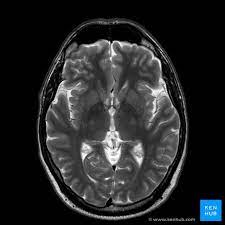

Every journey to health begins with a single step, and for Rajesh Sharma, that step was a brain MRI at Vision Diagnostic Center. Rajesh, a 45-year-old software engineer from Bengaluru, had been suffering from chronic headaches and occasional dizziness for over a year. Despite numerous visits to various doctors, his condition remained undiagnosed, leaving him and his family in a state of constant worry and frustration.

The MRI scan was quick and non-invasive, and within a few days, Rajesh had his results. The scan revealed a small, benign tumor pressing against his optic nerve, which was the cause of his symptoms. Armed with this knowledge, his doctors could now formulate a targeted treatment plan.

For Rajesh, the brain MRI was life-changing. The accurate diagnosis provided by Vision Diagnostic Center allowed his medical team to address the root cause of his symptoms effectively. Treatment began immediately, and within a few months, Rajesh’s headaches and dizziness had significantly reduced. More importantly, the emotional burden of uncertainty was lifted. He could focus on his recovery and get back to living his life fully.

Rajesh’s case is not unique. Many individuals suffer from undiagnosed neurological conditions that can severely impact their daily lives. The brain MRI service at Vision Diagnostic Center offers a beacon of hope for these individuals, providing accurate and timely diagnoses that can lead to effective treatments.

Priya, a 32-year-old school teacher from Chennai, had been battling severe migraines for years. Despite trying various medications and therapies, her condition persisted, affecting her ability to teach and enjoy her personal life. A visit to Vision Diagnostic Center for a brain MRI revealed an issue with the blood vessels in her brain, which was the underlying cause of her migraines. With this information, her doctors could prescribe a more effective treatment plan, drastically reducing her migraine episodes and improving her quality of life.